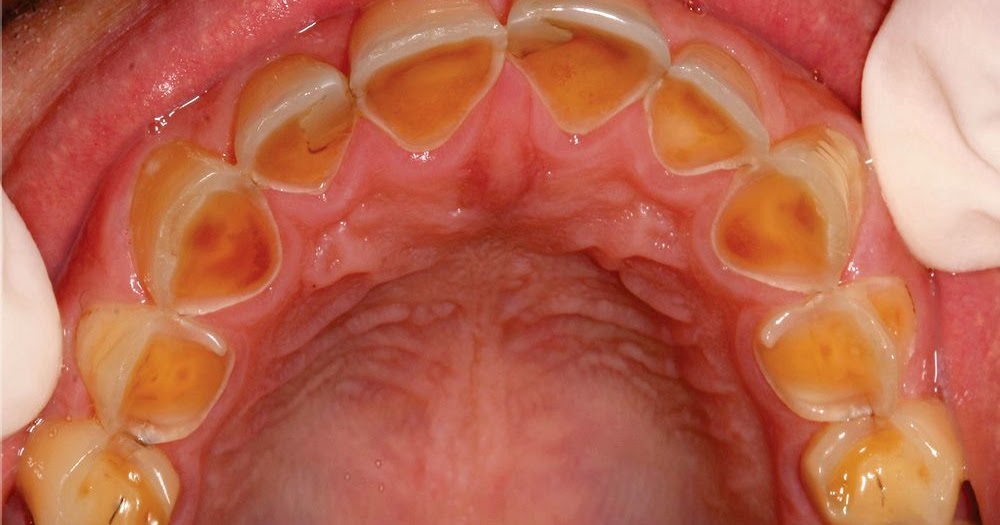

From pocketdentistry.com

Diagnosis of Dental Erosion Pocket Dentistry Dental Erosion. Definition Classification And Links Dental erosion involves the softening of the tooth surface by acidic substances of intrinsic or extrinsic origin, or a combination of both. The nomenclature and classification of dental erosion commonly used in the dental literature are summarized. The nomenclature and classification of dental erosion commonly used in the dental literature are summarized. They are based on etiology (extrinsic, intrinsic, idiopathic),. Dental Erosion. Definition Classification And Links.

From www.semanticscholar.org

Table 2 from Dental erosion. Definition, classification and links Dental Erosion. Definition Classification And Links European journal of oral sciences , volume 104. They are based on etiology (extrinsic,. The nomenclature and classification of dental erosion commonly used in the dental literature are summarized. Dental erosion involves the softening of the tooth surface by acidic substances of intrinsic or extrinsic origin, or a combination of both. They are based on etiology (extrinsic, intrinsic, idiopathic), on. Dental Erosion. Definition Classification And Links.